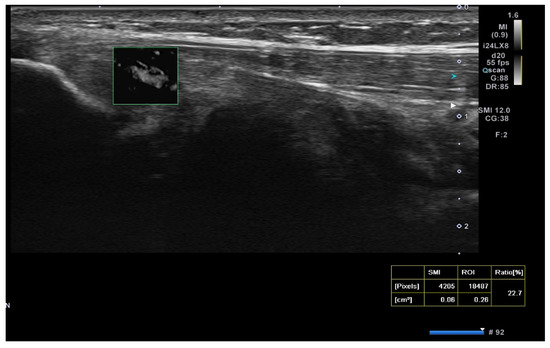

Ultrasound (USG) evaluations were conducted jointly by two specialists following the clinical diagnosis. The physicians performing the USG were blinded to the patients’ clinical outcomes and treatment details. The USG procedure was repeated three months post-treatment. Color Doppler imaging (frame rate 10–15 Hz) and superb microvascular imaging (SMI; frame rate > 50 Hz) were performed using the Toshiba Aplio 500 USG system with a high-frequency linear array transducer. Vascular activity on color Doppler imaging was graded on a scale of 0 to 4: Grade 0 = no activity, Grade 1 = single vessel, Grade 2 = Doppler activity < 25%, Grade 3 = Doppler activity 25–50%, and Grade 4 = Doppler activity > 50% [19] (Figure 2).

Figure 2.

Ultrasound images illustrating vascularity grading in lateral epicondylitis using Doppler imaging: (A) Grade 1: single-vessel activity; (B) Grade 2: Doppler activity ≤ 25%; (C) Grade 3: Doppler activity between 25 and 50%; and (D) Grade 4: Doppler activity ≥ 50%.